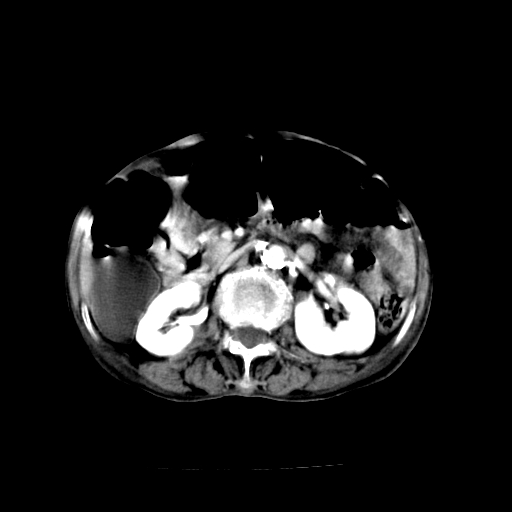

女,68岁,腹胀、恶心两周,先做ct平扫,当时家属不同意强化,6天后家属要求增强扫描。

1、胃窦癌; 2、局灶性脂肪肝。

1、胃窦癌?建议行胃镜!; 2、局灶性脂肪肝。

1)胃窦壁厚,考虑胃窦癌?建议行胃镜检查。 2)局灶性脂肪肝。